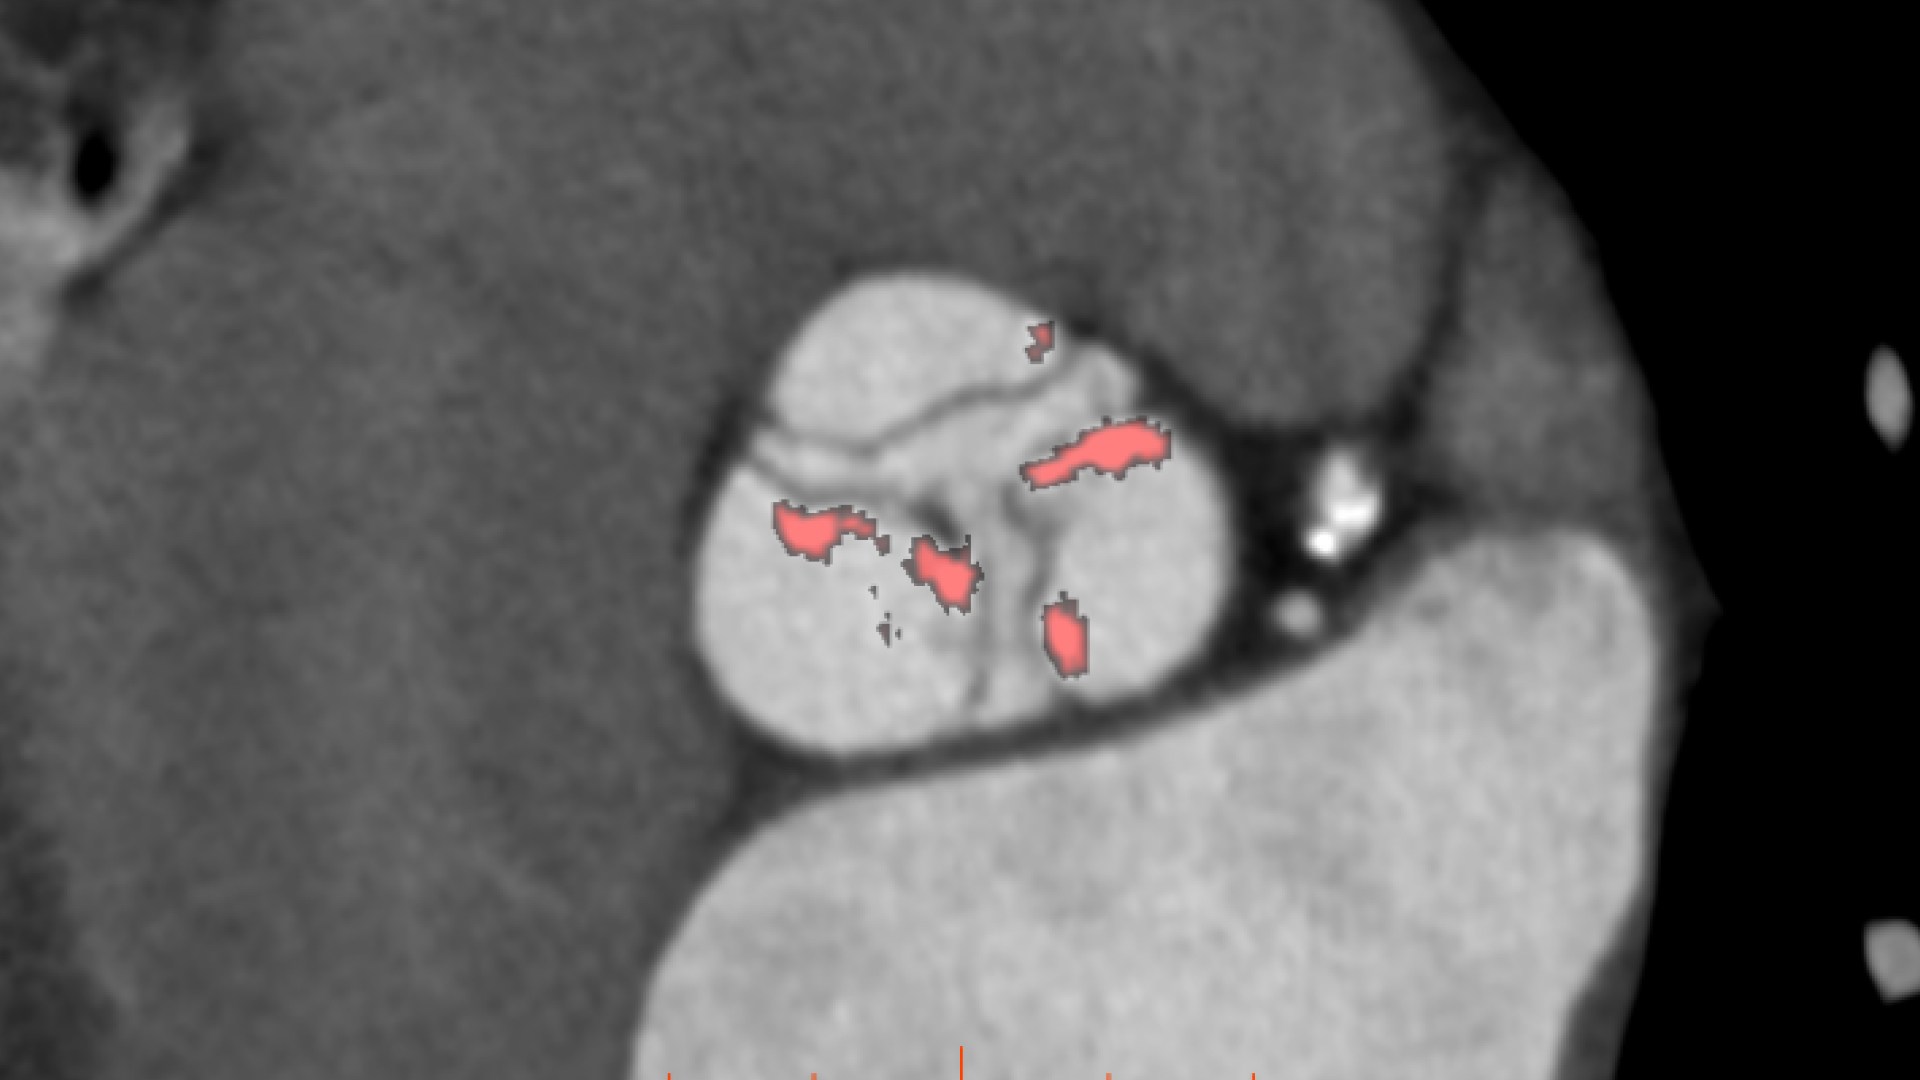

• Automated aortic segmentation and preliminary orientation to aortic annular plane

• Automatic estimate of aortic valve calcium volume measurement